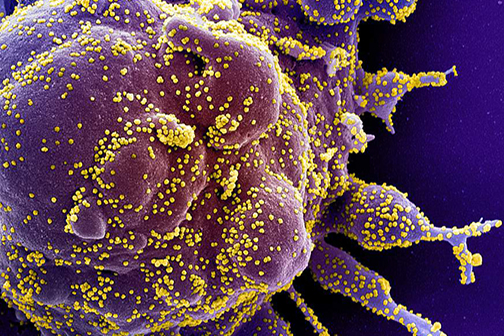

LSU Health New Orleans Study Reports Compound Blocks SARS-CoV-2 and Protects Lung Cells

Research conducted at LSU Health New Orleans Neuroscience Center of Excellence reports that Elovanoids, bioactive chemical messengers made from omega-3 very-long-chain polyunsaturated fatty acids discovered by the Bazan lab in 2017, may block the virus that causes COVID-19 from entering cells and protect the air cells (alveoli) of the lung. More